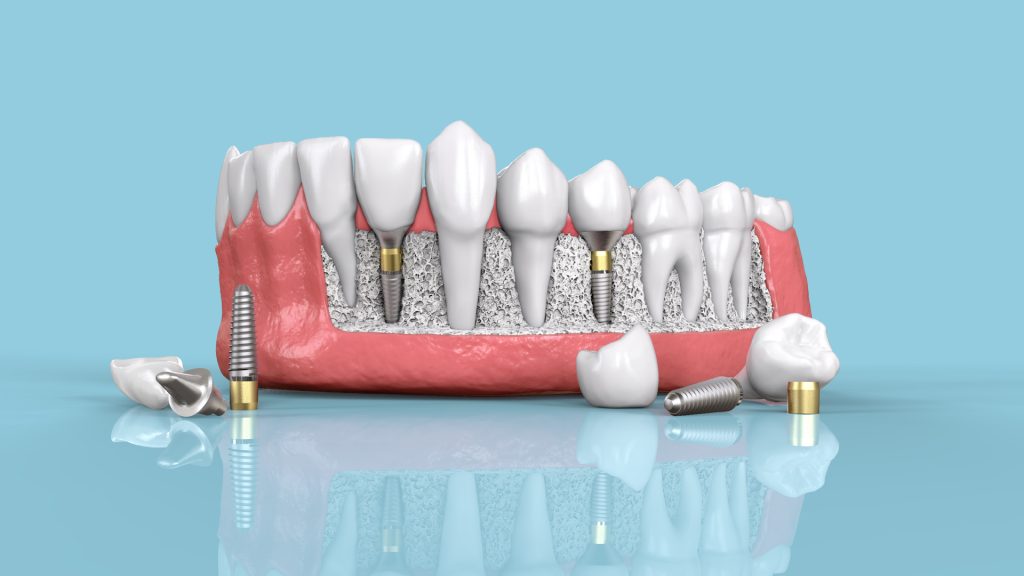

If you are searching for Dental Implants in Pune,...

A confident smile can transform your personality and with...

Finding the best dental clinic in Pune for orthodontic...

Looking for the best orthodontist in Pune. Orthodontic treatment...

If you’re searching for a Dentist Near Me or...

A perfect smile not only boosts confidence but also...

When it comes to your child’s dental health, choosing...